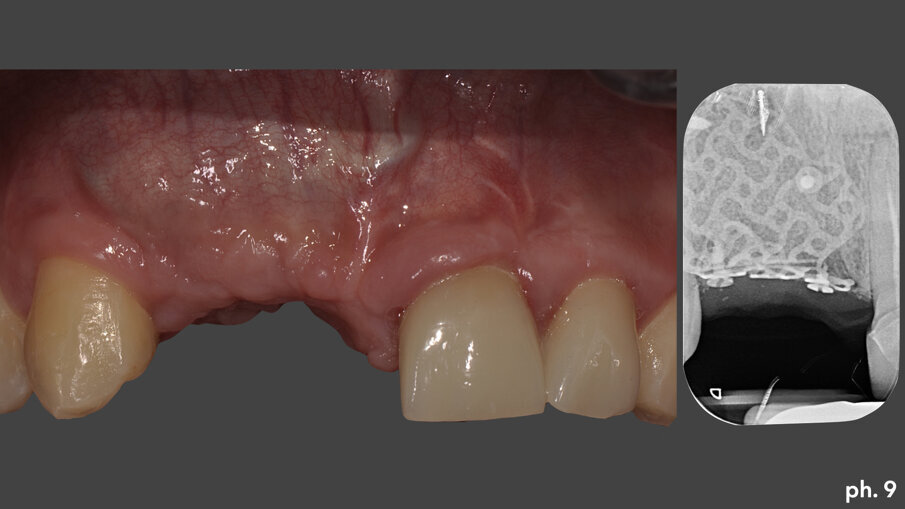

Una volta riempita la griglia con il mix di osso eterologo e autologo, la stessa è stata posizionata a livello del difetto e stabilizzata tramite l’utilizzo di viti di fissazione autofilettanti (Figg. 6, 7). Il grado di stabilità di queste griglie in titanio customizzate CAD/CAM è assolutamente elevatissimo, così come il loro grado di precisione. Stabilizzata in maniera perfetta la griglia, la stessa è stata ricoperta con uno strato di Geistlich Mucograft in modo da permettere la miglior maturazione possibile dei tessuti molli in fase di guarigione (Fig. 8). Al momento della chiusura del lembo è stato necessario effettuare un’incisione per il rilascio del periostio per ottenere una guarigione per prima intenzione, aspetto fondamentale affinché la maturazione di tali presìdi risulti perfetta. Il tempo di guarigione suggerito dalla letteratura prima della rimozione della griglia è di circa otto mesi; personalmente aspetto sempre 12 mesi prima di inserire impianti in una zona di osso rigenerato, e così è stato anche in questa situazione. L’immagine numero 9 rappresenta la guarigione a un anno di distanza e la relativa radiografia di controllo (Fig. 9). L’attesa così prolungata porta a far sì che la fase chirurgica della rimozione delle griglie in titanio sia l’aspetto più complesso di tutto il trattamento. Questo perché le aderenze di tipo fibroso che si creano tra i tessuti molli e la griglia stessa rendono difficile l’asportazione soprattutto a livello palatale e linguale (Fig. 10).

Dopo aver rimosso le viti di fissazione, la griglia stessa viene tagliata e separata in due porzionilungo la linea predefinita in senso longitudinale. Le stesse vengono poi rimosse delicatamente avvalendosi dell’aiuto di uno scollaperiostio e di un bisturi (Fig. 11). A questo punto una volta denudato il piano osso e valutata la sua qualità e quantità, possiamo passare all’inserimento degli impianti che in questo caso è stato effettuato in tecnica classica, senza l’ausilio di una mascherina per un inserimento computer guidato. Gli impianti scelti nella risoluzione di questa situazione sono due impianti Straumann BLT 4,1 x 10 mm (Fig. 12). Una volta inseriti gli impianti si è provveduto ad effettuare un assottigliamento del lembo palatino5; per permettere al paziente una miglior detersione dei presidi implanto-protesici, oltre che per consentirci l’utilizzo della porzione epitelio connettivale rimossa per ispessire coronalmente il tessuto gengivale nella zona di inserimento degli impianti. Eliminata chirurgicamente la porzione epiteliale del prelievo, abbiamo stabilizzato quella connettivale a livello osseo crestale utilizzando una sutura riassorbibile che ancorasse il tessuto al periostio (Fig. 13). L’aumento in senso verticale del tessuto cheratinizzato è evidenziato dall’immagine numero 14 dove possiamo valutare il livello coronale del tessuto molle prima della rigenerazione, la linea bianca, al momento della rimozione della griglia, la linea arancione, e infine alla maturazione dell’innesto di tessuto connettivo, la linea di colore verde (Fig. 14). Una volta maturati i tessuti molli sono stati quindi inseriti quattro elementi provvisori singoli, dall’elemento 1.2 all’elemento 2.2, di cui due su impianti e due su denti; le modifiche nel tempo di questi provvisori secondo la tecnica della compressione dinamica, ci hanno permesso di condizionare la guarigione degli stessi tessuti molli6 prima di passare alla fase di protesizzazione definitiva. I manufatti protesici definitivi sono quattro corone singole in zirconio-ceramica su impianti e su elementi naturali: in particolare le corone su 1.1 e 1.2 sono avvitate agli impianti (Fig. 15).